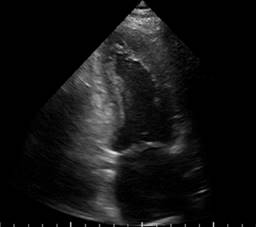

A transthoracic echocardiogram was performed that showed septoapical, apical, inferior apical akinesia, no thinned cardiac segments. Left ventricular ejection fraction (LVEF) 45%, type 1 diastolic dysfunction E/A 0.6, E/e 10, normal dimensions of the right heart chambers with normal right ventricular ejection fraction at rest. Systolic pulmonary artery pressure 26 mmHg, estimated by tricuspid reverse gradient. No pericardial effusion at rest (Figures 1 to 3). The patient evolved to be hemodynamically stable, so a stress echocardiogram was performed to search for viability/residual ischemia on the 6th day after admission to hospitalization. A 5-stage protocol was initiated, starting at 5 μg/kg/min, reaching 20 μg/kg/min. The patient persisted with septoapical and apical akinesia and developed an ischemic response due to developing basal and medial inferior hypokinesia. No changes were recorded in the electrocardiogram at this dose of dobutamine. Esmolol 30 mg intravenous single dose was administered at the beginning of the recovery phase and the study was terminated. In first minutes of recovery, the patient showed sudden deterioration in alertness and pulseless electrical activity. The echocardiogram showed pericardial effusion with a hematic appearance and echocardiographic data of tamponade (Figures 4 to 6). The patient presented cardiorespiratory arrest, so intravenous fluids were administered and an emergency pericardiocentesis was performed, achieving expansion of the right ventricle but with rapid formation of a new pericardial effusion. Later on, he presented asystole which did not revert to basic or advanced cardiovascular resuscitation.